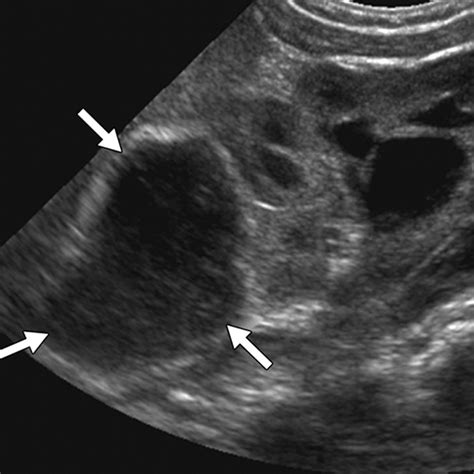

Ultrasound Non-invasive imaging to view soft tissues and identify fluid-filled cysts.

Because the abdomen contains a dense arrangement of structures, relying on a physical "self-exam" is rarely sufficient. A doctor will typically correlate physical findings with diagnostic imaging. For instance, an ultrasound might distinguish between a solid tumor and a fluid-filled cyst, while a CT scan provides the necessary detail to assess whether the mass in stomach involves surrounding blood vessels or lymph nodes. In some cases, a biopsy—the removal of a small tissue sample—is the only definitive way to characterize the cellular nature of the mass.